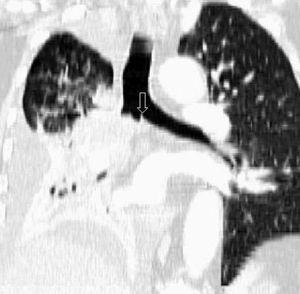

Fig. 1.--T3. (A) Reconstrucción multiplanar (MPR) de tomografía computarizada (TC) torácica con contraste con ventana de pulmón. Atelectasia completa del lóbulo inferior derecho secundario a tumor endobronquial situado a menos de 2 cm de la carina (flecha hueca). (B) La misma reconstrucción con ventana de mediastino muestra el tumor (flechas) diferenciado de la atelectasia (asterisco). Derrame pleural (DP).